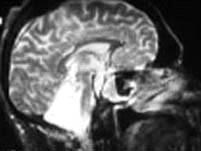

根据图示考虑是何种疾病 ( )A、小脑发育不良B、无脑畸形C、扁平颅底D、Arnold-Chiari畸形E、小脑扁桃体肿瘤

问题 根据图示考虑是何种疾病 ( )

选项 A、小脑发育不良 B、无脑畸形 C、扁平颅底 D、Arnold-Chiari畸形 E、小脑扁桃体肿瘤

答案 A